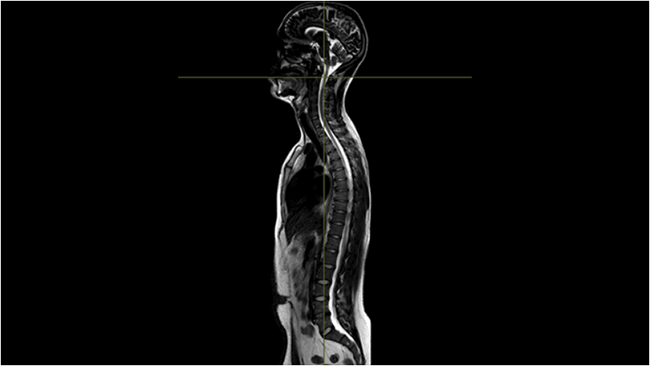

Úng dụng được sử dụng để tái tạo dữ liệu cột sống thông qua các góc khác nhau, đặc biệt hữu ích cho phân tích cột sống phức tạp, chẳng hạn như lập kế hoạch điều trị vẹo cột sống.